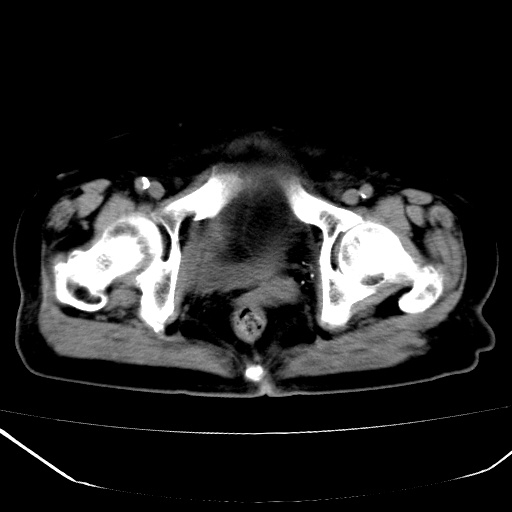

患者,女,74岁,无不适,b超示盆腔包块。

子宫前上方巨大脂性肿物,肿物边缘为较厚软组织密度影,其内缘欠光整,脂性密度中央见结节状软组织密度影“漂浮”,肿物与子宫前壁关系密切,考虑1脂肪瘤2皮样囊肿3肌瘤脂样变

ct值-90hu